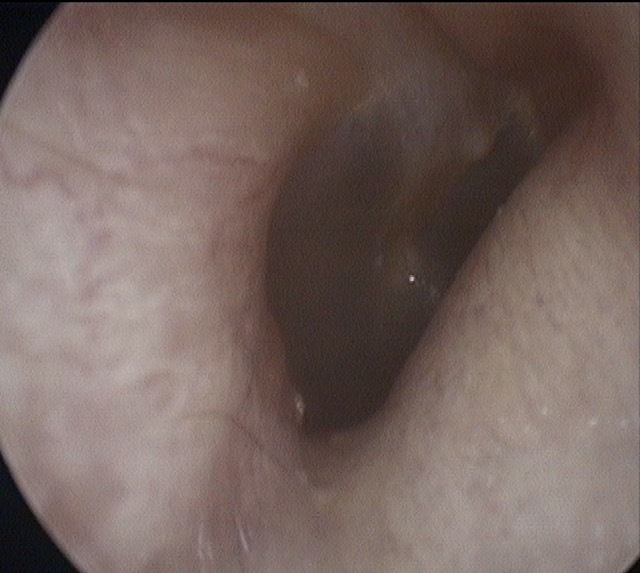

Atelectasis/Retraction

Ear Canal

Tympanic Membrane